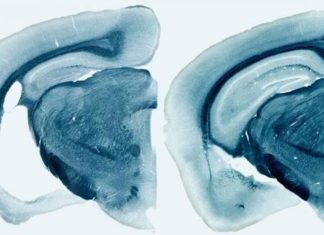

Reducir los niveles de proteína ApoE es la clave para prevenir o detener el alzhéimer

La proteína ApoE es responsable de que los ovillos neurofibrilares de proteína tau sean tóxicos para las neuronas cerebrales.